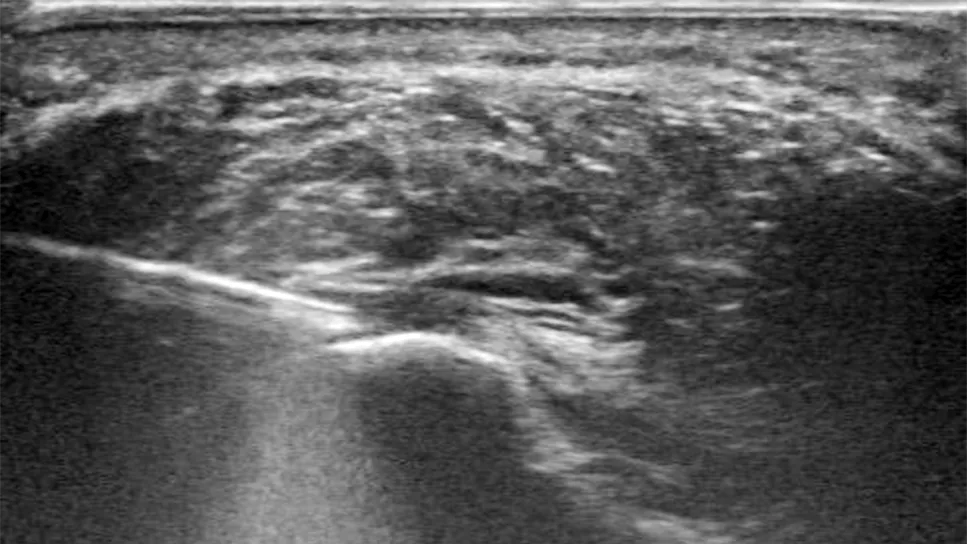

Hydroresection of plantar fascia

Shown above: Under ultrasound guidance, a slender hydroresection tool applies a pressurized, high-velocity stream of saline to debride diseased plantar fascia tissue.

Instead, the patient was referred for an interventional therapy, hydroresection. Using ultrasound guidance and a slender tool applying a pressurized, high-velocity stream of saline, the plantar fascia’s diseased tissue could be debrided in the office.

After positioning the patient, Dr. Patel used ultrasound to locate inflammation in the plantar fascia. (Tissue degeneration can cause areas of the plantar fascia to become hypoechoic, swollen with poorly formed collagen and water.)

Next, lidocaine and epinephrine were injected into the plantar fascia for anesthesia and to help control bleeding. Dr. Patel then made a tiny incision into which he inserted the hydroresection needle. The needle shot saline into the diseased, fibrotic tissue, resecting it while simultaneously using suction to remove it, leaving healthy tissue intact.